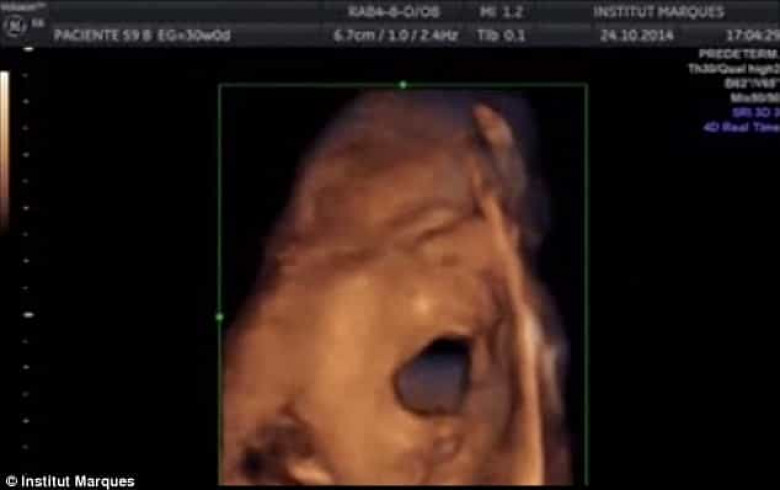

ԼԱՅՖԲժիշկների անցկացրած նորագույն ուսումնասիրության արդյունքները փաստում են, որ մայրական արգանդում գտնվող պտուղն ունակ է լսել արտաքին ձայներն արդեն 16 շաբաթականում:

Ինչպես նշում է The Daily Mail-ը, Բարսելոնայի Մարկեսի անվան համալսարանի գիտական թիմն ապացուցել է, որ պտուղն ունակ է ոչ միայն լսել ձայները, այլև` դիմախաղով ու բերանի շարժումներով արձագանքել դրան։ Ըստ մասնագետների՝ պտղի նման պահվածքը ենթադրում է, որ նա «երգում» է։

Աղբյուրը մանրամասնում է, որ նախկինում բժիշկները կարծում էին, որ պտուղը սկսում է լսել միայն 16-26 շաբաթականում։